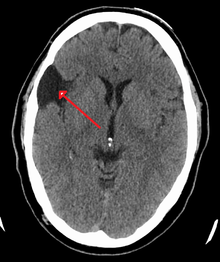

Diagnosis

Diagnosis is principally by MRI. Frequently, arachnoid cysts are incidental findings on MRI scans performed for other clinical reasons. In practice, diagnosis of symptomatic arachnoid cysts requires symptoms to be present, and many with the disorder never develop symptoms.